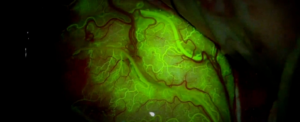

У нещодавньому дослідженні вчені застосували цей підхід для доставки хіміотерапевтичних препаратів до пухлин головного мозку у мишей. Вони виявили, що звукові хвилі змогли відкрити гематоенцефалічний бар’єр і дозволили лікам проникнути вглиб пухлини. Це призвело до значного зменшення розміру пухлини та покращення показників виживання мишей.